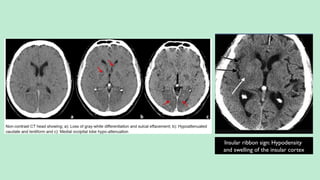

Insular ribbon sign: Hypodensity

and swelling of the insular cortex

2. Blurring and Indistinct GW matter Interface:

a. Insular Ribbon Sign.

b. Disappearing BG Sign.

Seen in about (50-70%) cases in the first 3 hours at the least.

Obscuration of the lentiform nucleus so-called

disappearing basal ganglia sign

MCA dot sign